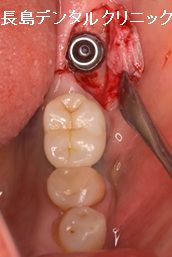

黄色い矢印の部分にインプラントを1本埋入します。

術後なるべく腫れないように必要最低限の歯茎の切開に努め埋

入する部位の骨の形状や歯茎の厚みなどを確認しインプラント

最適な位置に埋入していきます。